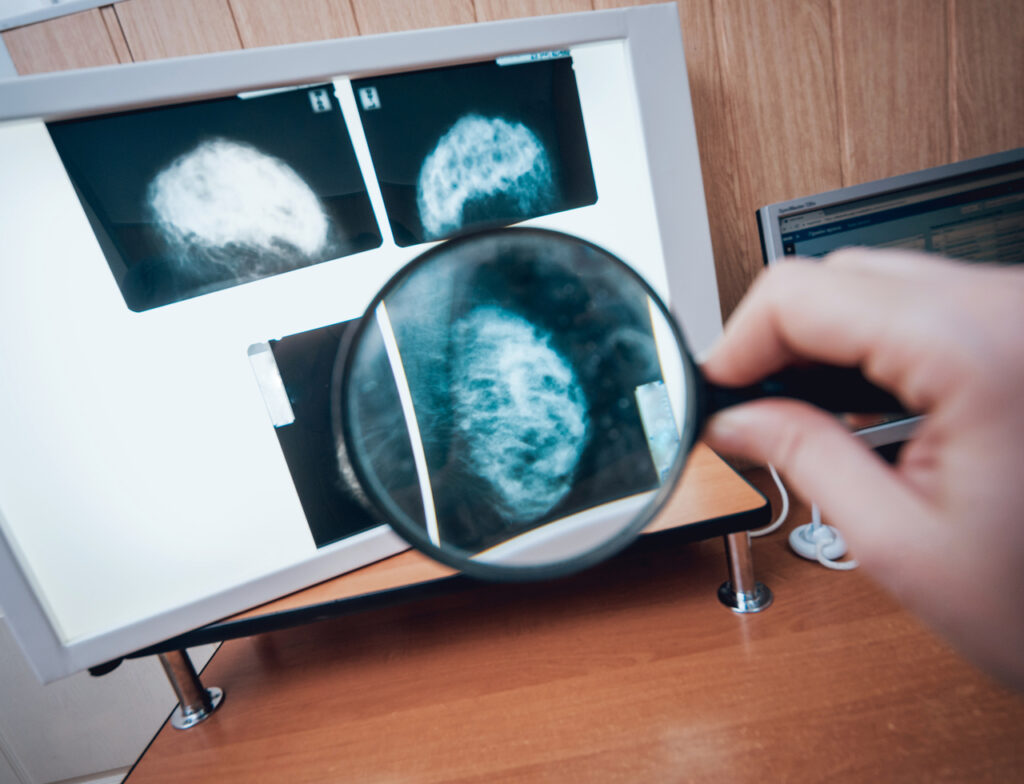

If you’ve felt a suspicious lump on your breast, the main concern at hand is whether a portion of your breast is cancerous. After finishing a mammogram, the doctor may prescribe a follow-up procedure called a breast biopsy.

As stated before, a breast biopsy is a procedure for evaluating suspicious lumps or mass. The tissue sample is removed for laboratory testing. Your doctor will typically order a biopsy if they are concerned about the results of a breast ultrasound or mammogram.

When you first hear about a biopsy, it can be daunting, especially because it involves penetrating a needle through the skin to obtain tissue samples. But it is considered a relatively-pain free procedure. Despite the potential requirement of imaging tests like mammograms, MRI, and ultrasounds beforehand, it is only through a breast biopsy where cancerous cells are identified.